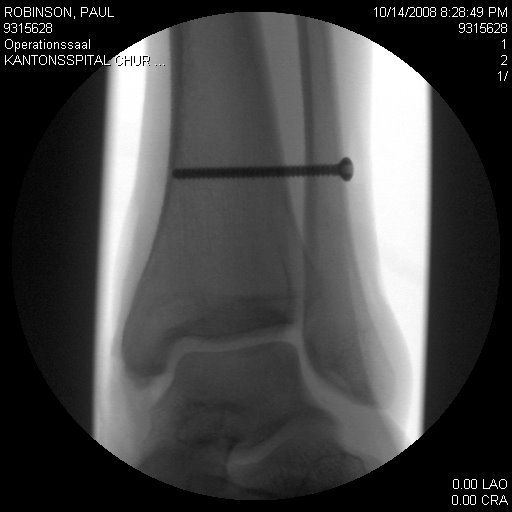

После перелома Пол Робинсон чувствует себя уже немного лучше. Боль спала, опухоль лодыжки проходит. Отец Пола помог оборудовать гараж для тренировок и поддержания хоть какой-то формы сына. Вот небольшое видео после травмы. Так же на этом видео показано прохождение болдеринга в Мэджик Вуд "The Riverbed" (fb 8b/ V13).